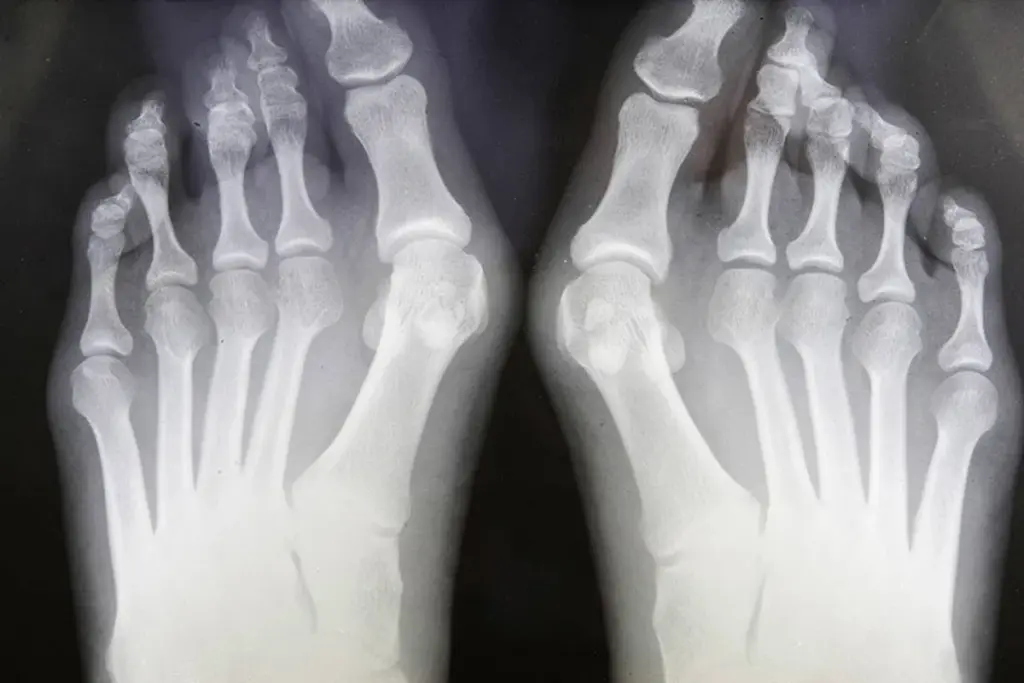

The disease is characterized by chronic, symmetric, and erosive synovitis inflammation of the synovial lining of the joints. In a healthy state, the synovium is a delicate membrane responsible for nourishing cartilage and lubricating the joint. In Rheumatoid Arthritis, this membrane undergoes a pathological transformation, thickening into a destructive tissue mass known as pannus. This pannus invades and erodes the underlying cartilage and bone, leading to the joint deformities historically associated with the disease. However, the contemporary understanding of this process focuses heavily on the cellular mediators driving this destruction, specifically the cytokines such as Tumor Necrosis Factor alpha and Interleukin-6. By targeting these specific pathways with biologic agents, clinicians can interrupt the signal cascade that drives inflammation, thereby preserving the joint’s structural integrity and maintaining the potential for future regenerative interventions.

• Osteoclastogenesis: The inflammatory milieu stimulates osteoclasts, the cells responsible for bone resorption, leading to the characteristic bone erosions seen in advanced imaging.